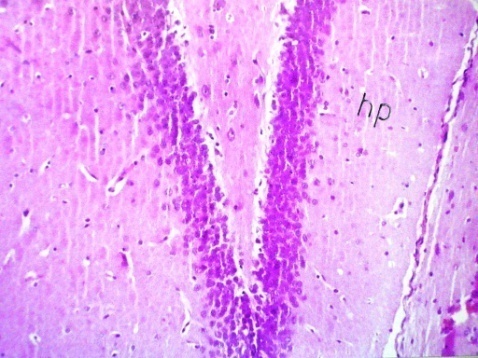

Microscopic examination of brain tissue sections of rats in the negative control group showed no histopathological alteration, with normal histological structure of the hippocampus (Fig.1). Photomicograph of brain tissue sections of rats in the AD-induced group showed neuronal degeneration and oedema with gliosis in the hippocampus (Fig.2). Also, cerebral encephalomelacia and plaques formation have been observed in the hippocampus of the AD-induced group (Fig. 3). Photomicograph of brain tissue sections of rats in the AD-induced group treated with rivastigmine showed intact normal histological structure of the hippocampus (Fig.4). Microscopic examination of brain tissue sections of rats in the AD-induced group treated with B. serrata (137.5 mg/kg b. wt) showed normal histological structure of hippocampus and striatum (Fig. 5). While, photomicrograph of brain tissue section of rats in the AD-induced group treated with B. serrata (68.75 mg/kg b. wt) showed neuronal degeneration and odema in the hippocampus (Fig. 6).

Photomicrograph of brain tissue sections of AD-induced rats showed neuronal degeneration and oedema with gliosis in the brain. Also, cerebral encephalomelacia and amyloid plaques formation have been detected in AD-induced rats. Klatzo et al. [82] stated that the intracerebral administration of Al in the experimental animals induced neurofibrillary degeneration and appearance of tangle-like structures that are similar to the NFTs found in the brains of AD patients. Praticó et al. [83] found that oral administration of Al caused marked increase in the amount of β-amyloid both in its secreted and accumulated forms. Also, Al could increase the deposition of senile plaques in AD-model mice transfected with human APP gene (Tg 2576). Rodella et al. [84] also in consistent with other study demonstrated that oral Al supplementation caused the accumulation of β-amyloid and impaired the spatial learning memory in AD-model mice.